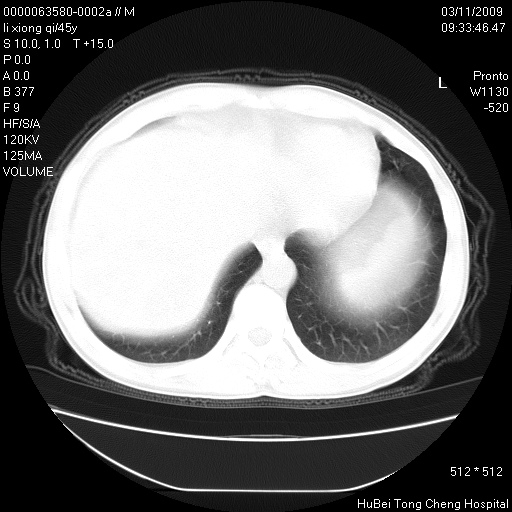

患者 男,45岁。胸痛,咳嗽伴痰中带血1月余。

临床诊断:肺结核?

胸部ct轴位平扫(层厚10mm,螺距1.5,重建间隔10mm),图像如下: